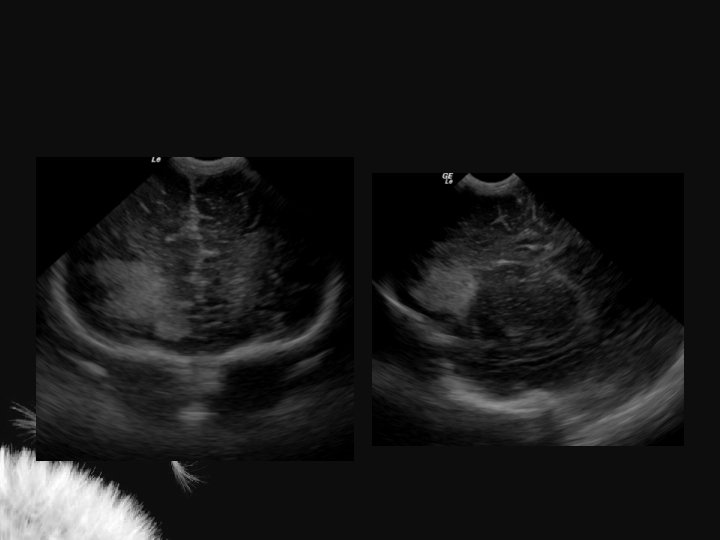

Hidrocefalia benigna da infância – sinal da veia cortical positivo

Coleção subdural – sinal da veia cortical negativo